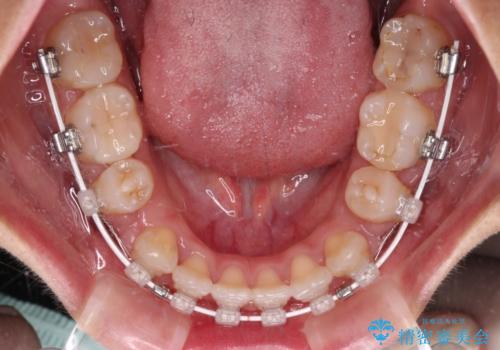

- 矯正装置

- ハーフリンガル

裏側装置での矯正治療は、上顎前歯の正中のズレをまっすぐに改善することが難しいのですが、きれいに整えることができました。

補助装置を用いて抜歯したスペースを速やかに閉じたことで、短期間での治療となりました。